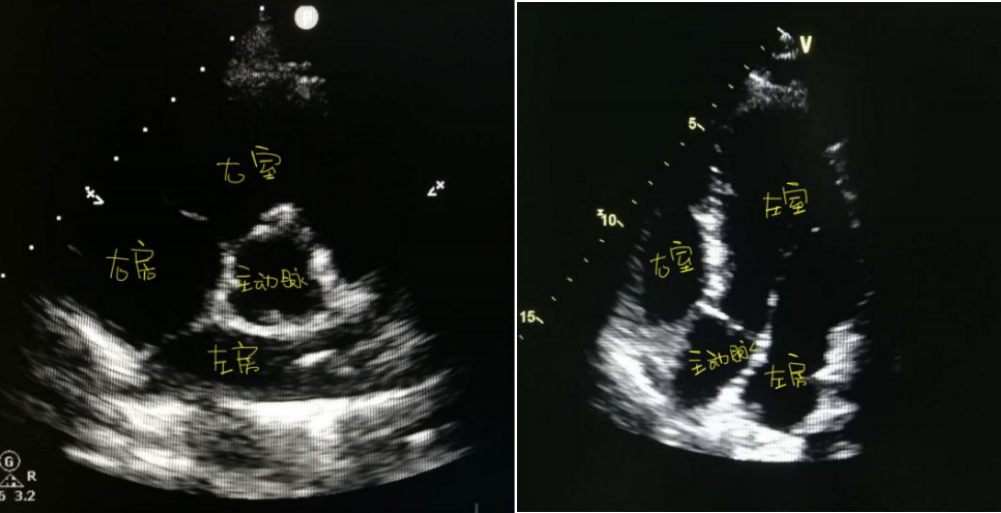

1、墙:在心脏的这套房子里,拥有四间房子,形成了一个两层小楼房,上层为“心房”,下层为“心室”。左侧两间就是左心,右侧的两间是右心。正常情况下,左右两侧的房间是不相通的,有墙体(间隔)隔开。心脏彩超就是主要看看房间的大小、墙体厚度、墙体的完整性。

2、门:心脏彩超还要负责检查心脏的四个“阀门”情况,这“阀门”就是心脏的瓣膜,包括主动脉瓣、肺动脉瓣、二尖瓣、三尖瓣。检查瓣膜的打开和关闭是否顺利,有没有出现打不开和(或)关不紧的情况,如果这门开不大,出入空间就会变小,这就叫“瓣膜狭窄”;门关不严,叫“瓣膜关闭不全”,如果这门掉下来了这就叫 瓣膜脱垂。